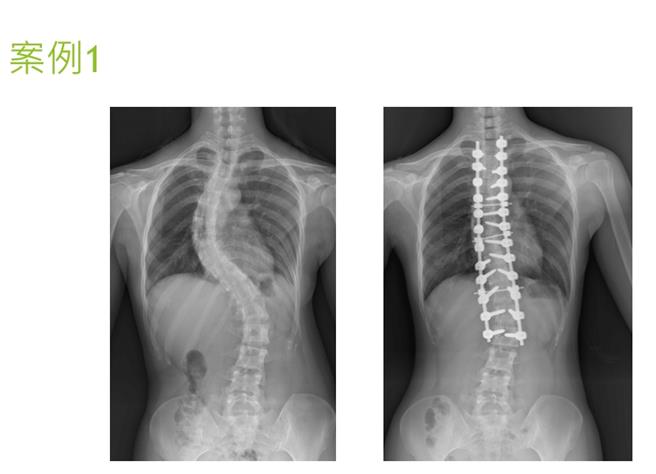

台中荣总创新利用AR扩增实境眼镜搭配术中导航技术进行脊椎侧弯矫正手术,病患严重的脊椎侧弯,术后角度趋近正常。(台中荣总提供/冯惠宜台中传真)

根据临床调查,台湾青少年脊椎侧弯的发生率约在5-10%,其中3%病人必须透过手术治疗,但传统手术受限于视野,仍有伤到神经血管造成瘫痪风险;台中荣总创新利用AR扩增实境眼镜搭配术中导航技术进行脊椎侧弯矫正手术,迄今已累积15名患者,病患脊椎侧弯的角度平均达79.57度,最大甚至达124度,而术后角度皆降至20度、甚至达0度,手术中骨钉置入的准确度超过95%以上。